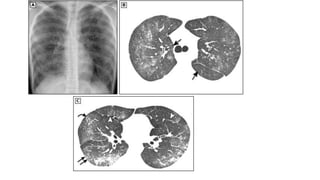

• #22 Chest radiograph (A) shows a bilateral reticulonodular pattern. High-resolution computed tomography (CT) image at the level of the main bronchi (B) demonstrates bilateral ground-glass opacities and centrilobular nodules (arrows). High-resolution CT scan at the level of the basal segmental bronchi (C) shows centrilobular nodules (straight arrows), branching opacities (tree-in-bud pattern; curved arrow), ground-glass opacities, small foci of consolidation, and mild thickening of the interlobular septa (arrowheads). The patient was a 20-year-old man with Mycoplasma pneumoniae pneumonia.